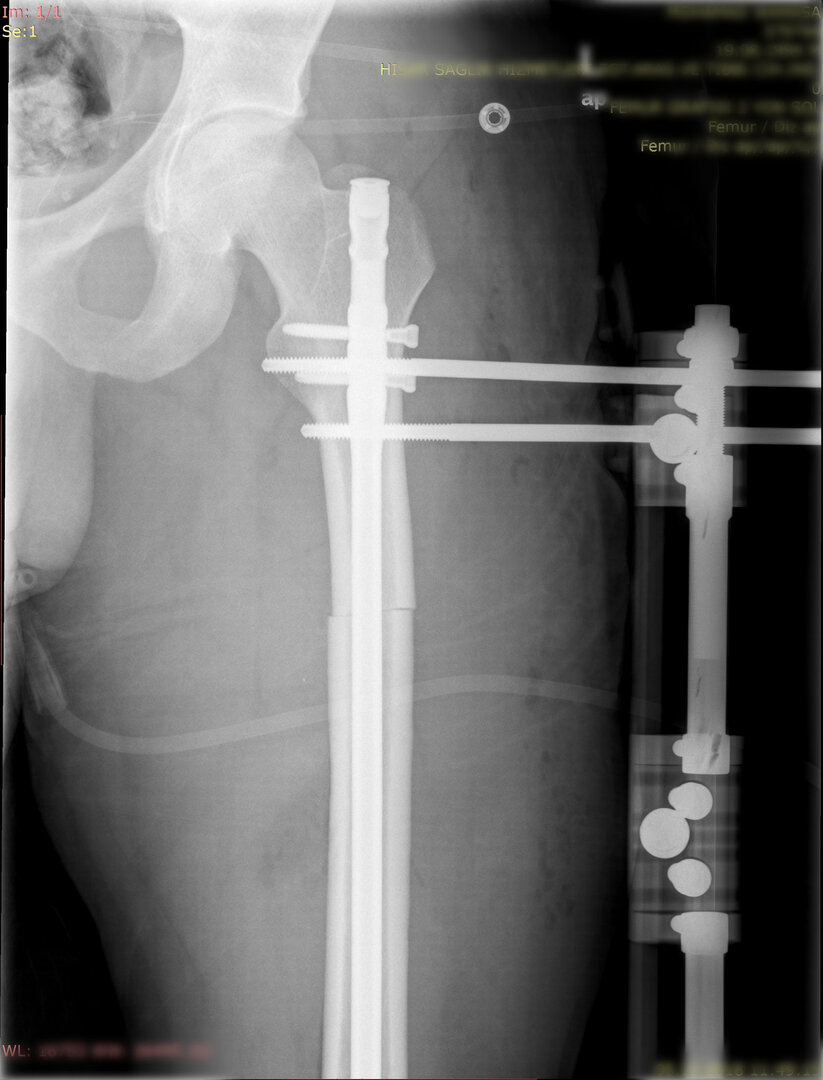

1. Kombine yöntem ile uzatma (LON-lengthening over nail- Çivi üzerinden uzatma):

Bu yöntemde uzatılacak kemiğin içerisine osteotomi sonrası bir intramedülller çivi yerleştirilir ve dışarıdan tek yönlü bir eksternal fiksatör kemiğe adapte edilir. Dışarıdan yine günde 4 defa çeyrek tur açarak 1 mm uzatma sağlanır. Uzatma miktarına ulaşılınca çivi kilitlenir ve uzayan bölümün sertleşmesi beklenir.

Görüntüleri büyütmek için üzerine tıklayınız.

Görseli büyütmek için üzerine tıklayınız. Görseli büyütmek için üzerine tıklayınız. Radyografi görseli büyütmek için üzerine tıklayınız. Radyografi görseli büyütmek için üzerine tıklayınız. Radyografi görseli büyütmek için üzerine tıklayınız.